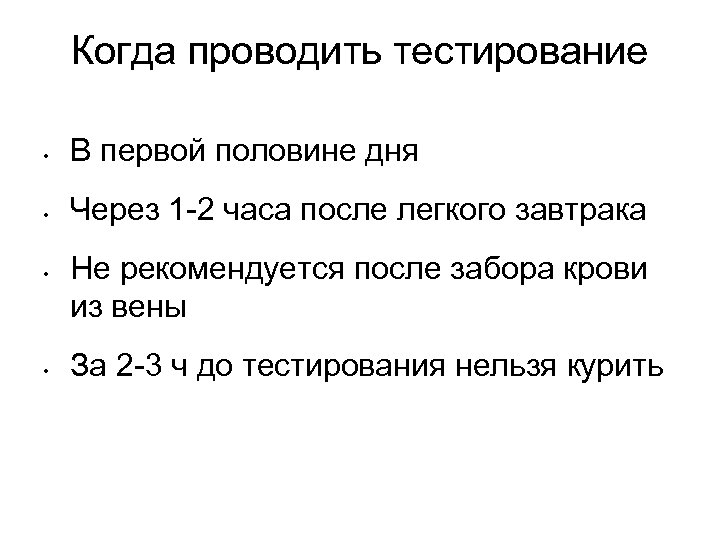

Когда проводить тестирование • В первой половине дня • Через 1 -2 часа после легкого завтрака • • Не рекомендуется после забора крови из вены За 2 -3 ч до тестирования нельзя курить

Когда проводить тестирование • В первой половине дня • Через 1 -2 часа после легкого завтрака • • Не рекомендуется после забора крови из вены За 2 -3 ч до тестирования нельзя курить